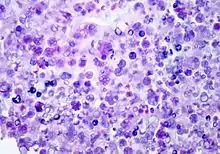

P. wickerhamii has a round to elliptical cell shape measuring 3–11 µm in diameter. The organism has thick wall (theca) with internal septations that form the small wedge-shaped endospores, which are arranged radially and moulded (morula-like form).[1]. Reproduction is asexual by release of the spores from the sporangia, which can occur every 5-6 hours in ideal conditions.[2]

Diagnosis can be made through culture of diseased tissue in Sabouraud dextrose agar or by visualization of sporangia containing sporangiospores on tissue biopsy (using hematoxylin/eosin, GMS, or PAS histochemical stains). The organism incites a chronic granulomatous inflammation with infiltrate of histiocytes, lymphocytes, giant cells and occasional eosinophils.

Differential diagnosis: Protothecal sporangia may be confused with Coccidioides immitis, which are much larger